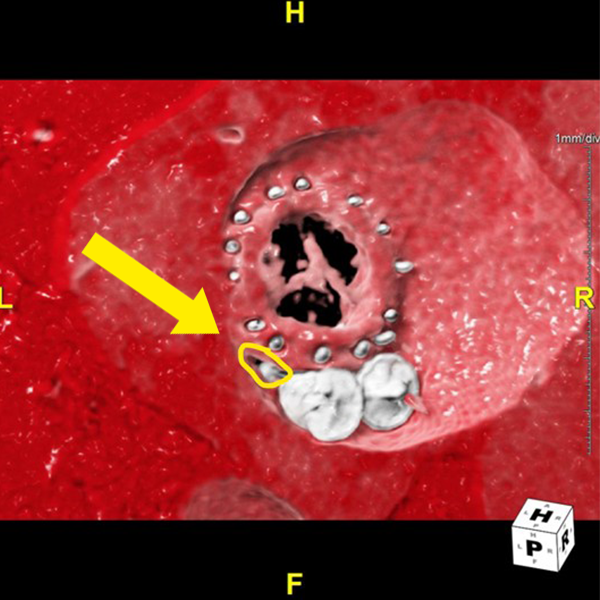

Figure D: A close-up view of the paravalvular leak, used to confirm its size and location before proceeding with 3D printing.